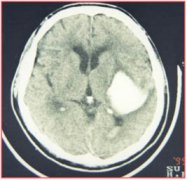

重獲健康不是夢—記孫阿姨高血壓病病史及糖尿病10年引起右側(cè)

腦卒中是由于腦部血管突然破裂或因血管阻塞導致血液不能流入...